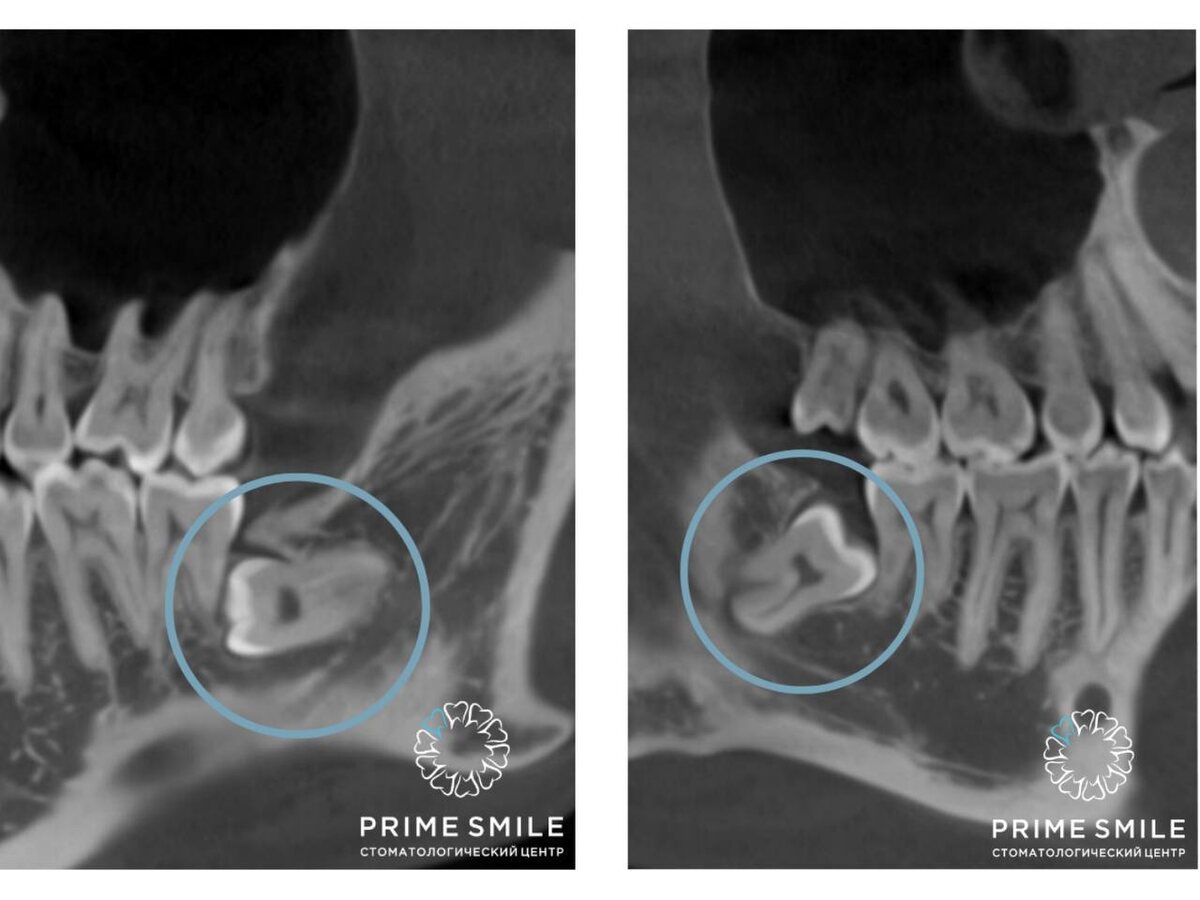

Все дело в эволюции. С течением времени челюсть человека уменьшалась. Связано это с различными процессами, в том числе с тем, что мы кардинально поменяли свой рацион, когда научились готовить пищу с помощью тепловой обработки. Итак, челюсть в процессе времени уменьшилась, но количество зубов на ней сохранилось. По этой причине начались различные патологии в росте зубов, особенно крайних восьмерок. Они могут не прорезаться или прорезаться частично (ретинированные зубы), а также расти в неправильном положении, к примеру, не вверх, а в бок (дистопированные зубы). Часто зубы мудрости совмещают эти два качества – растут практически лежа в костной толще. На рентгене одного из наших пациентов это как раз хорошо видно.

Ретинированные дистопированные зубы мудрости на нижней челюсти